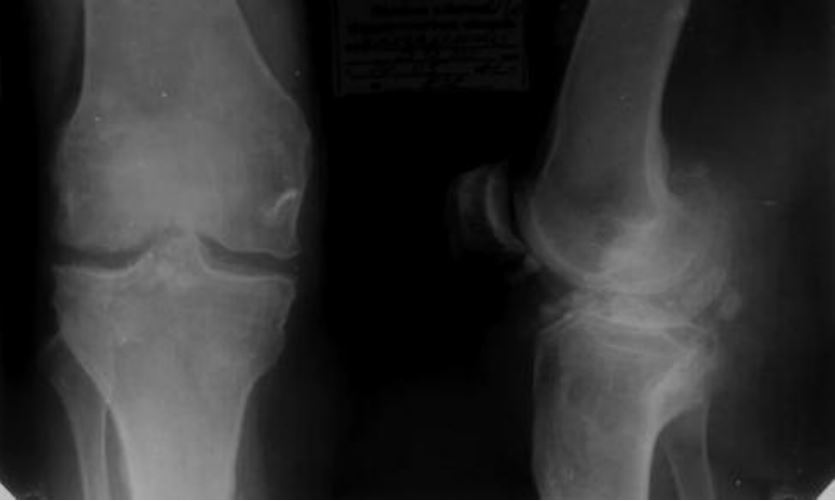

На полученных рентгенографических изображениях хондромные тела визуализируются в виде множественных шаровидных или овальных теней с четкими очертаниями. Но это исследование информативно только при наличии включений с обызвествленными участками.